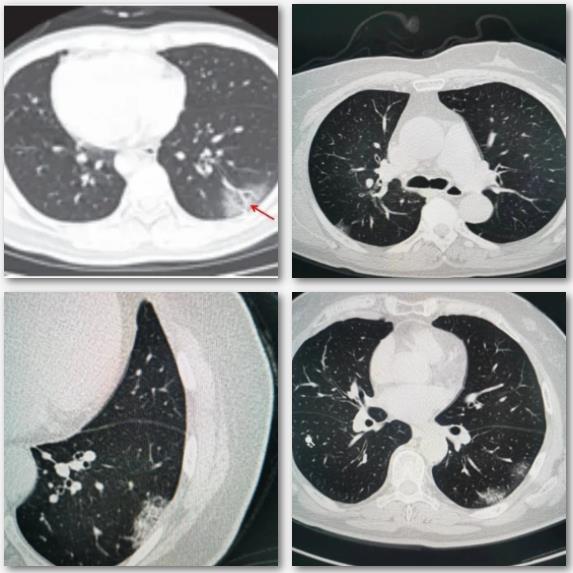

一、病灶分布特点

1.病灶以肺外围宽基底分布,背侧为主,以两肺下叶为著,与胸膜常紧贴。

2.病灶沿着胸膜下呈长条片状分布,长轴与胸膜平行,一般不引起胸膜反应。

3.病灶沿支气管血管束分布较多病灶常沿着支气管血管束分布,从外周向中央进展。

二、病灶形态特点

(一)直接形态特点表现

1.多叶多灶分布,病灶可同时散在于不同的肺叶、肺段。

2.单叶片状病灶,部分病人病灶局限于单叶成片状磨玻璃影分布。

3.孤立性结节样病灶,部分病灶成孤立结节样分布。

4.结节伴晕征,部分实性结节病灶周围出现磨玻璃密度影,边缘模糊,称为晕征。

5.细网格征铺路石征:在磨玻璃病灶内部常可见细网格状阴影,类似铺路石状,称为细网格征或铺路石征。

(二)间接形态表现特点

1.空气支气管征:实变肺组织内可见含气支气管正常穿行,未见明显狭窄和扭曲,少部分病例可以看到支气管壁增厚、管腔通畅,而晚期病变可以出现支气管牵拉、扭曲征象。

2.血管增粗征:在亚实性病灶内部清晰显示血管走行,部分血管管径增粗,甚至比近端更粗。

三、病灶密度绝大多数案例出现磨玻璃病灶,最低测得 CT 值约为-600Hu ;部分案例磨玻璃病灶与实性病灶共存。

四、少见征象:部分病例可见双侧胸腔积液;纵隔增大淋巴结肿大及心包积液。

五、进展期征象:大多数病例进展迅速,复查 CT 影像发生明显变化。表现为病灶数目明显增多,范围明显扩大,密度增高,病灶分布由外周向中央推进。

六、重症期征象:肺部病变一般在发病后14天左右达到高峰,少部分病例急剧进展,病变累及双侧全肺,呈“大白肺”(肺部受累面积超过70%)其内可见空气支气管征,双侧胸腔可有少量胸腔积液,临床纳入危重症管理。